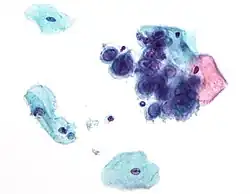

| Chlamydia trachomatis bacteria found in a pap test of the cervix in a case of chlamydia | |